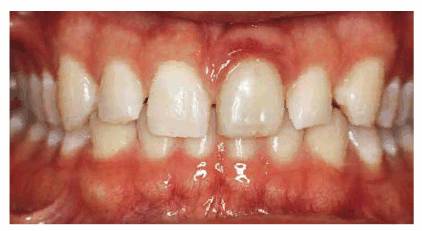

PROBLEM: This 21-year-old male model hesitated to smile because of his

diastemas (see Figures 23-14A, 23-14G, and 23-14I). The patient was also concerned about the appearance

Figure 23-14A: This 21-year-old male model performed both runway and photography modeling without smiling because he disliked the spaces in his teeth.